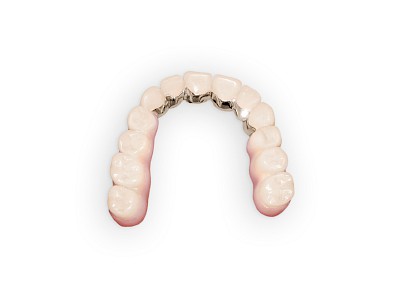

Prothese

Bei herausnehmbaren Prothesen werden Implantate eingesetzt, um den Halt und den Tragekomfort der Prothesen zu verbessern. Dazu kommen verschiedene Verbindungselemente zum Einsatz:

- Teleskope

- Kugelköpfe

- Tellerförmige Lokatoren

- Stege

- Magnete (selten)

Neben rein implantat-getragenen zahnärztlichen Versorgungen werden bei herausnehmbaren Prothesen Implantate auch in Sinne einer "strategischen Pfeilervermehrung" ergänzend zu eigenen Zähnen zur Verankerung eines Zahnersatzes genutzt.

Beispiele: Implantate und herausnehmbare Prothesen42 Bilder